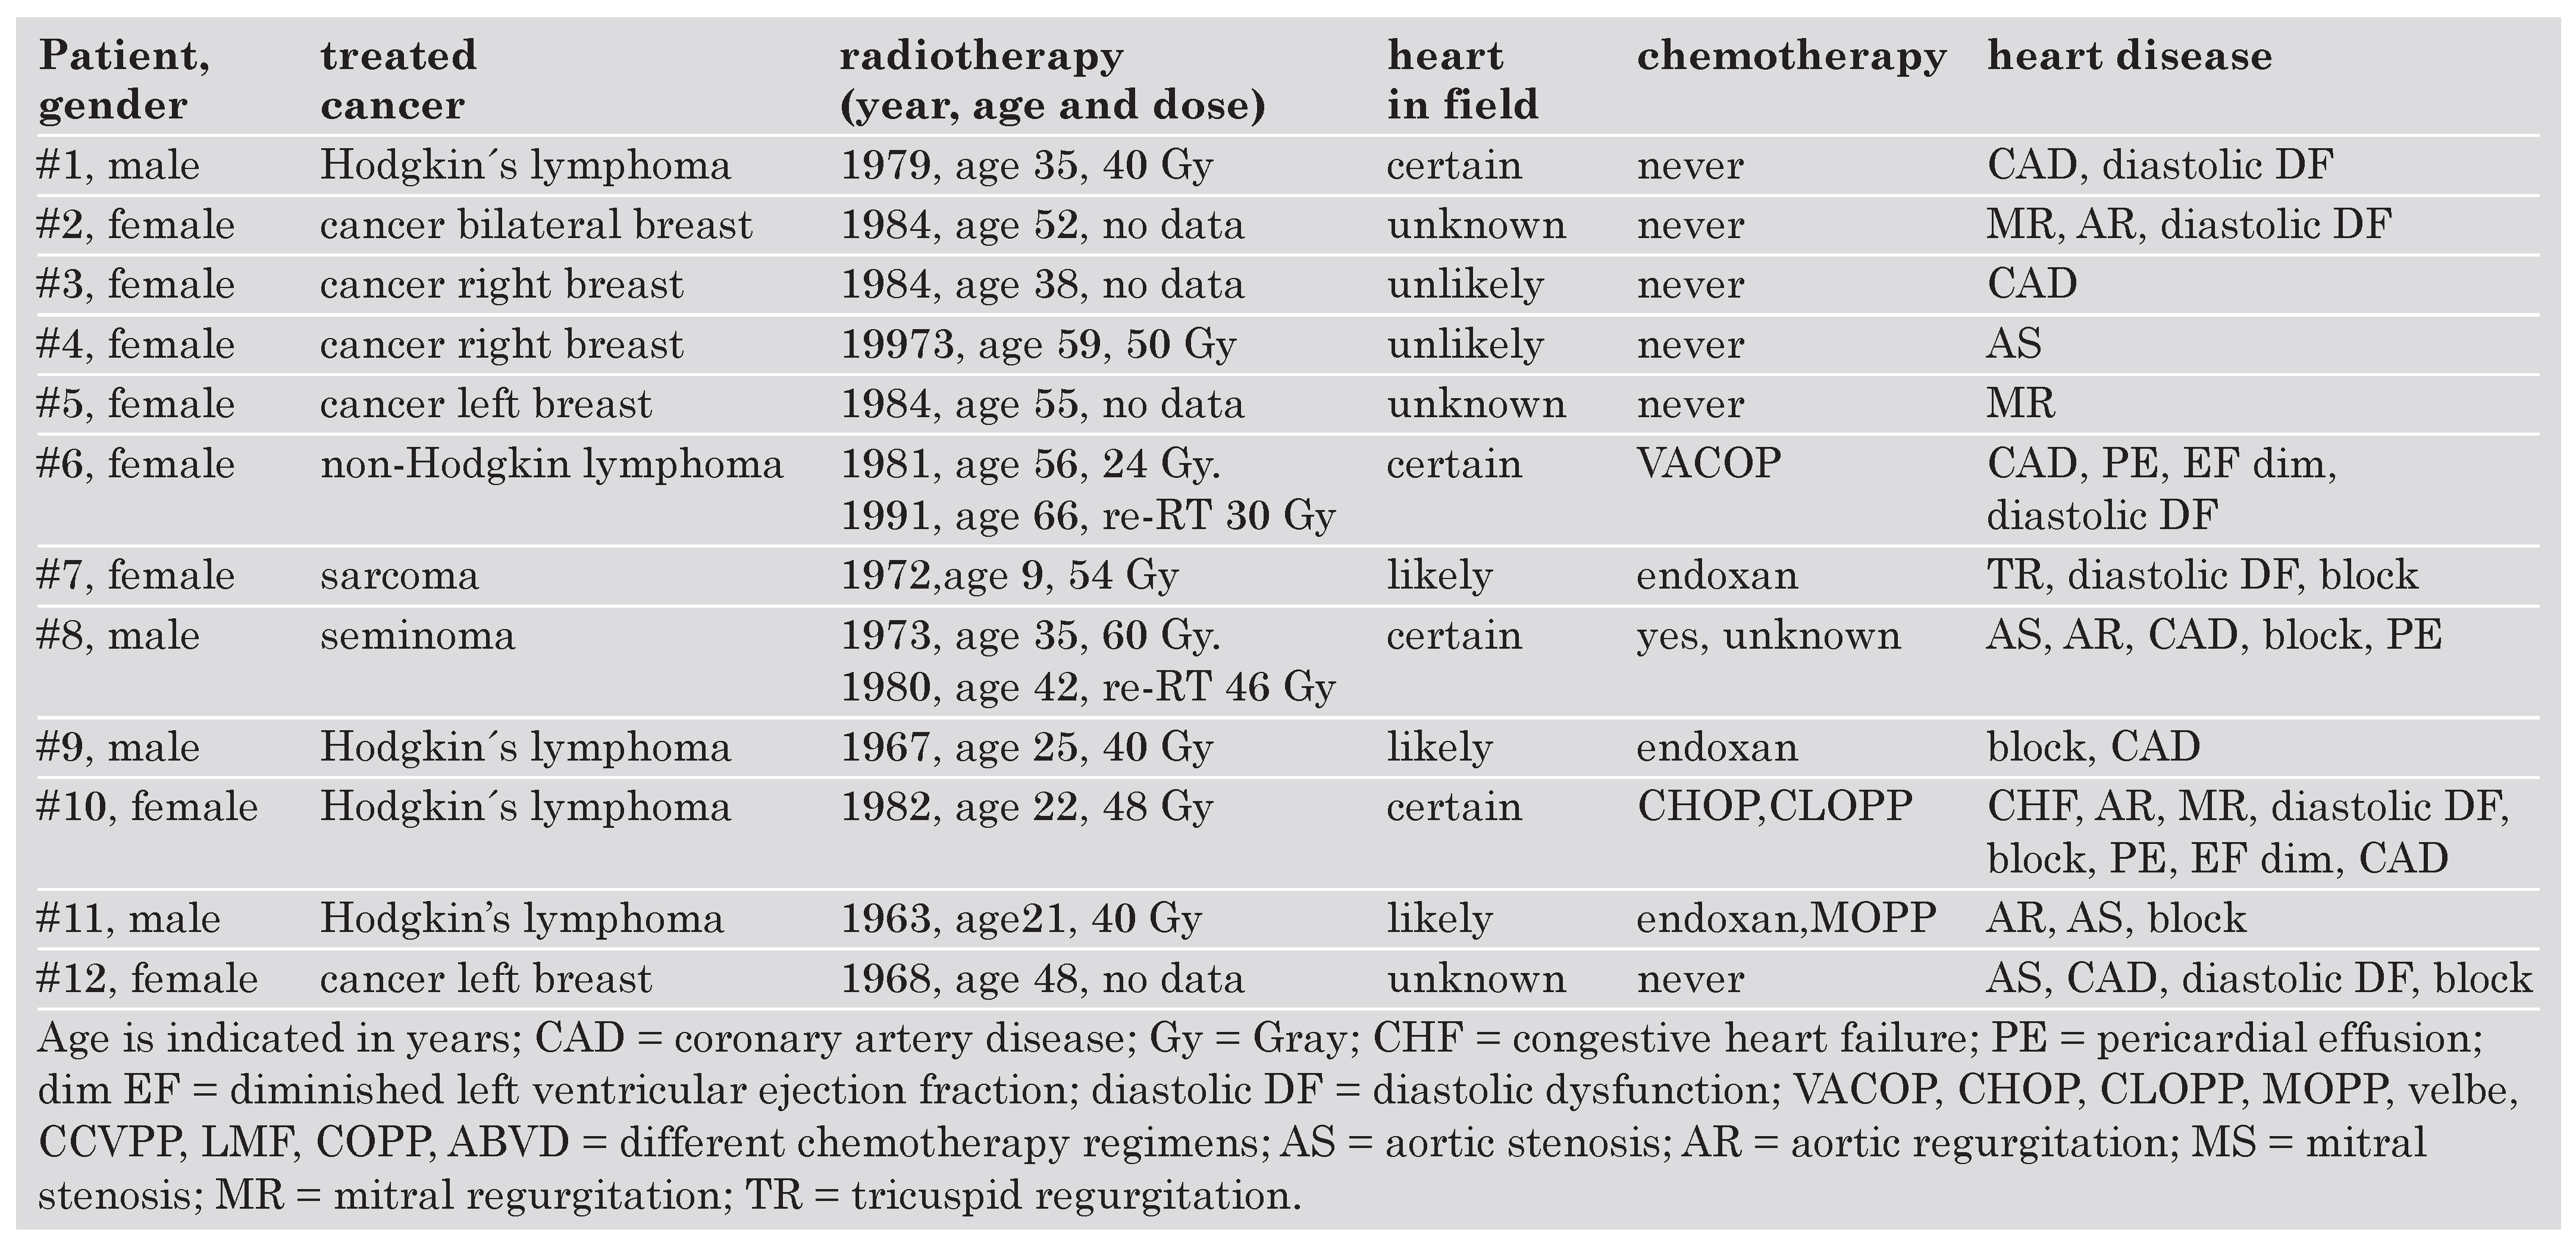

Clinical characteristics

|